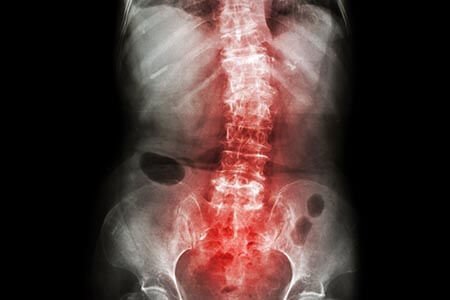

स्पोंडिलोआर्थराइटिस, जिसे स्पॉन्डिलाइटिस या स्पोंडिलोआर्थ्रोपैथी के रूप में भी जाना जाता है, निकट संबंधी गठिया रोगों का एक समूह है जो मुख्य रूप से जोड़ों और एन्थेसिस (स्नायुबंधन और टेंडन) को प्रभावित करता है। यह पीठ दर्द के साथ-साथ गर्दन, आंत, श्रोणि, आंखों और शरीर के बड़े जोड़ों में दर्द और सूजन की विशेषता है।

स्पोंडिलोआर्थराइटिस एक व्यापक शब्द है जो काफी हद तक रीढ़ से जुड़ा है, हालांकि, इसमें शरीर के अन्य क्षेत्रों की सूजन से संबंधित समस्याएं भी शामिल हैं। स्पोंडिलोआर्थराइटिस की सबसे आम स्थितियां हैं:

- आंक्यलोसिंग स्पॉन्डिलाइटिस विश्व का सबसे लोकप्रिय एंव iरीढ़ की हड्डी में सूजन और एंकिलोसिस (नई हड्डी का निर्माण) जिसके परिणामस्वरूप सूजन संबंधी पीठ दर्द होता है।

- अक्षीय स्पोंडिलोआर्थराइटिस (एक्सस्पा): यह एक व्यापक श्रेणी है जिसमें एक्स-रे में सैक्रोइलियक जोड़ों (रीढ़ के सबसे निचले हिस्से को श्रोणि से जोड़ने वाले जोड़) में विशेष सूजन वाले परिवर्तन वाले या बिना वाले लोग शामिल हैं।

- - रेडियोलॉजिक एक्सस्पा: स्पॉन्डिलाइटिस जिसमें सैक्रोइलियक परिवर्तन एक्स-रे पर प्रमुख होते हैं। एंकिलॉज़िंग स्पॉन्डिलाइटिस के लगभग सभी मामले इसी श्रेणी में आते हैं।